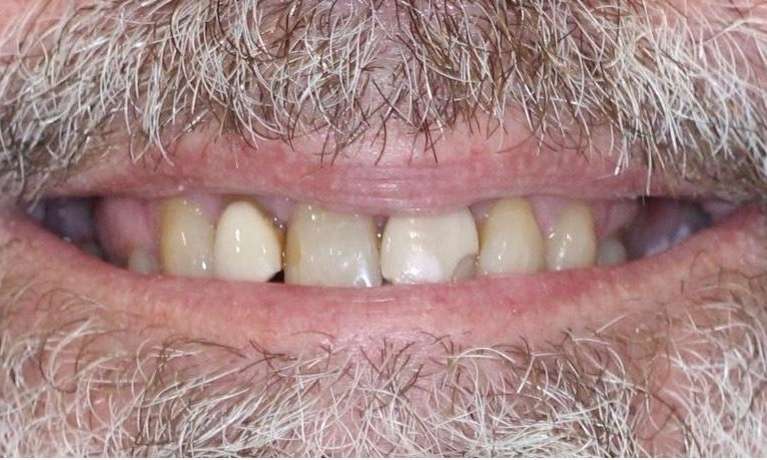

This patient presented with discolouration and uneven tooth shapes, eager to achieve a brighter, more uniform smile. Through the artistry of porcelain veneers, we were able to completely revitalise their smile.